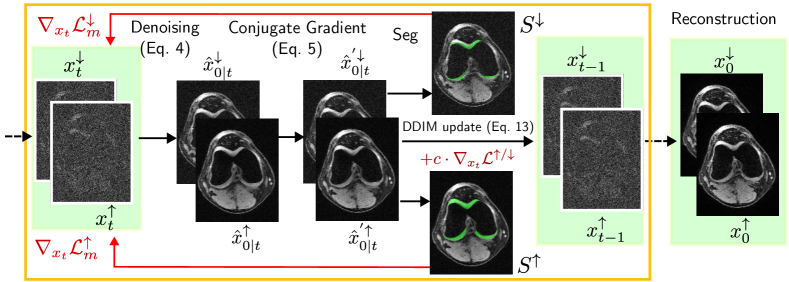

Refer to caption

Figure 2: Method explanation. For each inverse diffusion step t𝑡t, we calculate xt/subscriptsubscript𝑥𝑡superscriptabsent\nabla_{x_{t}}\mathcal{L}^{\uparrow/\downarrow} and include the gradient in the calculation of xt1subscript𝑥𝑡1x_{t-1}, in order to increase (decrease) the segmentation volume and to get an upper- and lower-bound segmentation (Ssuperscript𝑆S^{\uparrow} and Ssuperscript𝑆S^{\downarrow}).

The derived optimization objective can be used during the reverse diffusion process. We therefore calculate the gradient of msuperscriptsubscript𝑚\mathcal{L}_{m}^{\uparrow} (or msuperscriptsubscript𝑚\mathcal{L}_{m}^{\downarrow}, respectively) with respect to xtsubscript𝑥𝑡x_{t} at every step t𝑡t, to find the perturbation necessary to increase the optimization loss. We add the gradient xtmsubscriptsubscript𝑥𝑡superscriptsubscript𝑚\nabla_{x_{t}}\mathcal{L}_{m}^{\uparrow} (or xtmsubscriptsubscript𝑥𝑡superscriptsubscript𝑚\nabla_{x_{t}}\mathcal{L}_{m}^{\downarrow}, respectively) during the DDIM update in Eq. 6:

where b𝑏b is a small constant that we set to b=0.005𝑏0.005b=0.005 in our experiments. An ablation study on the effects of the parameter value can be found in the Appendix. A summary of our method is shown in Fig. 2.